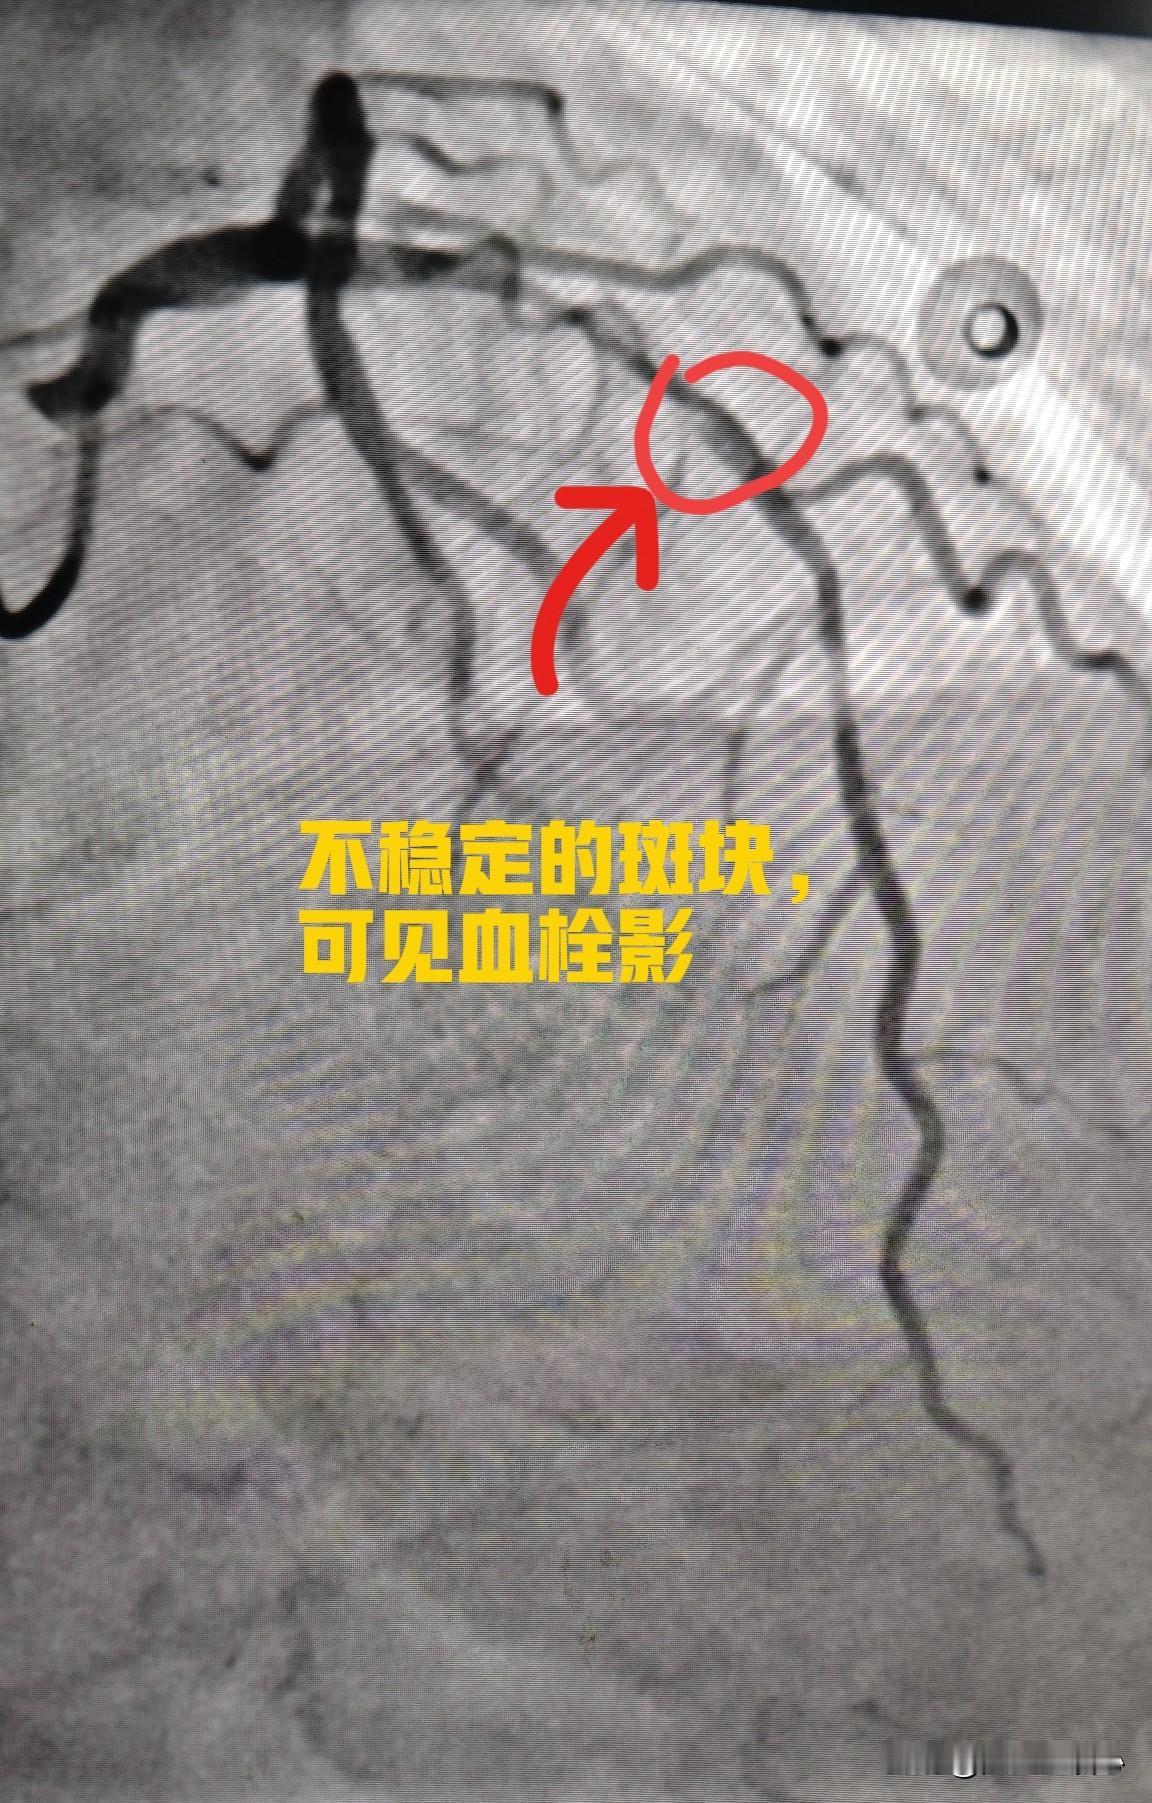

来看看心脏血管斑块破裂是什么样子的。一个 75 岁的男性患者,在医院就诊时,突发心脏骤停倒地,经胸外按压积极抢救后恢复意识。 紧急做了冠状动脉造影,发现是前降支中段一个不稳定斑块出现的破裂,局部有血栓形成。这就是导致患者突发意识丧失的原因。导丝通过前降支病变后,植入支架三枚,把斑块附近的有动脉硬化的血管全部覆盖,血流恢复通畅。 其实这里的狭窄本身并不严重,狭窄程度大约在 70% 左右。突然出现急性心肌梗塞,并不是说堵塞非常严重,而是一些不稳定的斑块突然破裂,导致的局部血栓形成,进而堵塞整个血管。 冠心病的治疗,一方面是预防血栓,另外一方面是尽量稳定动脉硬化斑块,让其不容易破裂。稳定斑块的方法,最主要的是降低低密度脂蛋白胆固醇,一旦发现有冠心病,最好把低密度脂蛋白胆固醇降低到 1.8 以下,最好降低到 1.4 以下。这样斑块才会更加稳定,不容易破裂,也就不容易突发急性心肌梗塞了。